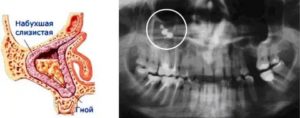

Наиболее частой причиной, по которой назначается операция на гайморовых пазухах, является гайморит — воспаление слизистого покрова верхнечелюстной пазухи, вследствие которого происходит скопление гнойного экссудата и формирование гиперпластических изменений слизистой оболочки.

Самой распространенной болезнью, прогрессирующей в этой области является гайморит. Но иногда в этот орган попадают посторонние предметы и вызывают ряд неприятных последствий.

Самую распространенную причину, после которой в гайморовой пазухе можно обнаружить инородное тело, следует искать в кабинете у стоматолога. Речь идет о пломбировании верхней челюсти.

Корни зубов расположены близко к слизистой оболочке пазух. При надавливании стоматолог может не рассчитать силы и продвинуть посторонний предмет в полость.

Это может случиться при установке пломбы и при наращивании стенки верхней челюсти для последующего внедрения имплантата.

Через некоторое время инородный предмет покрывается грибком и вызывает характерные симптомы. Происходит воспалительный процесс. До этого человек может и не заметить наличия проблемы.

Существует много названий, которыми часто пользуются доктора – мицетома, грибковый гайморит, грибковое тело, грибковый шар. Иногда используется диагноз – одонтогенный гайморит, что не совсем соответствует реальности. Что же такое грибковый гайморит? Механизм развития заболевания достаточно прост.

Наверняка каждый человек лечил зубы, и часто лечение сопровождается пломбировкой каналов зуба. Дело в том, что корни верхних зубов особенно 5 и 6-го часто вдаются в верхнечелюстную пазуху и прикрыты со стороны пазухи только слизистой оболочкой.

Таким образом, стоматолог, совершенно без злого умысла, проводя работу над корнем зуба, может проткнуть ее верхушку и протолкнуть пломбировочный материал в пазуху. Более того, иногда в пазуху может попасть даже фрагмент самого корня зуба или корень полностью. Вот тут и начинается самое интересное.

Сам по себе пломбировочный материал – совершенно безвредная субстанция. И он мог бы находится в пазухе годами, но не так все просто. Дело в том, что на поверхности слизистой оболочки пазухи обитают грибки, которые совершенно безвредны для нас.

Но когда появляется субстрат – пломбировочный материал, вокруг него начинает формироваться рост грибковой колонии. Со временем формируется так называемое грибковое тело, которое постепенно может заполнить всю пазуху и даже разрушить ее стенки. Нужно отметить следующие моменты: — Процесс развивается не быстро.